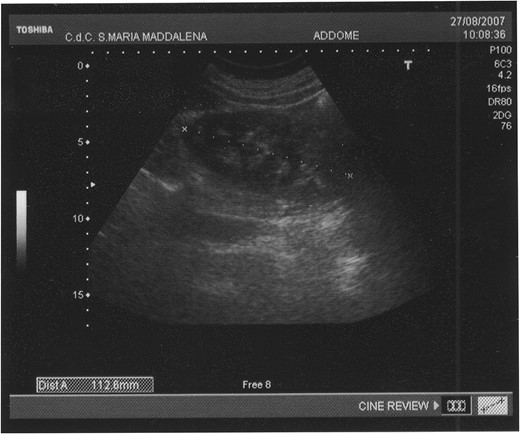

In July 2007, a 63-year-old white woman referred to a first-level Hospital for a palpable lesion in correspondence of right gluteus. She had not fever neither pain, but only a swollen area in perianal region. She was submitted to Ultrasounds (US), that showed an hypervascularized swelling that was interpreted as a voluminous hematoma (size 13 × 10 cm, thickness 4–5 cm), partially organized in the context of muscular structures of right gluteus (Fig. 1). After antibiotic therapy without any size regression, the patient was submitted to a Computed Tomography (CT) of abdomen and pelvis.

The abdominal ultrasound (US) shows an ovoid swelling, misinterpreted as a partially organized hematoma in the contest of the right gluteus maximus muscle.